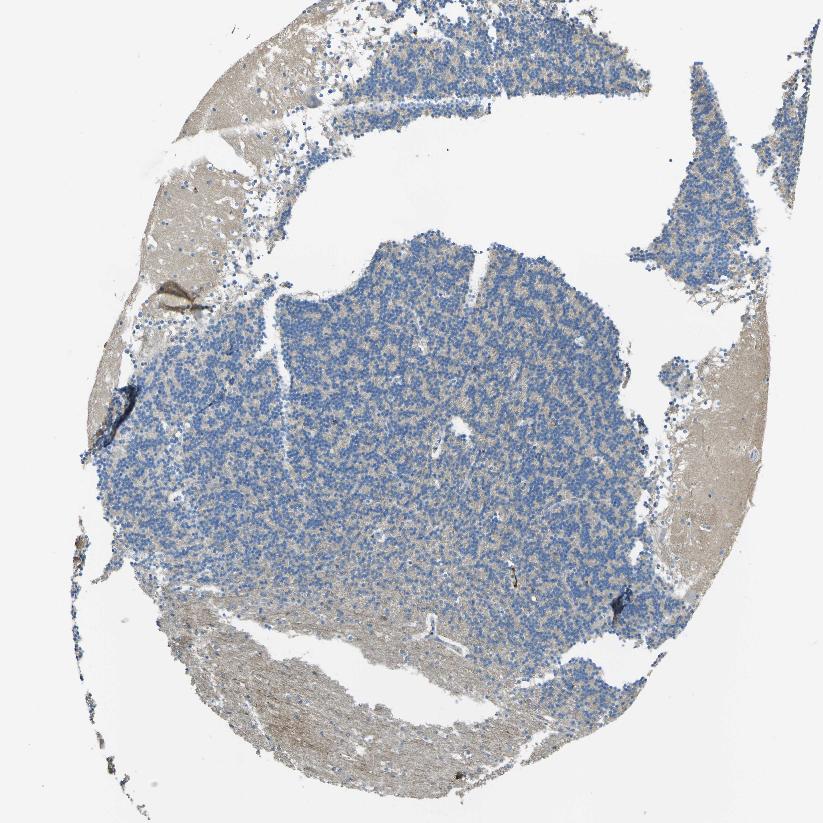

CEREBELLUM - Antibody stainingi

Antibody staining in the annotated cell types in the current human tissue is reported as not detected, low, medium, or high, based on conventional immunohistochemistry profiling in selected tissues. This score is based on the combination of the staining intensity and fraction of stained cells.

Each image is clickable and will lead to virtual microscopy that enables deeper exploration of all samples and also displays staining intensity scores, fraction scores and subcellular localization as well as patient and tissue information for each sample.

Antibody HPA013132

Purkinje cells Not detected

Cells in granular layer Low

Cells in molecular layer Low